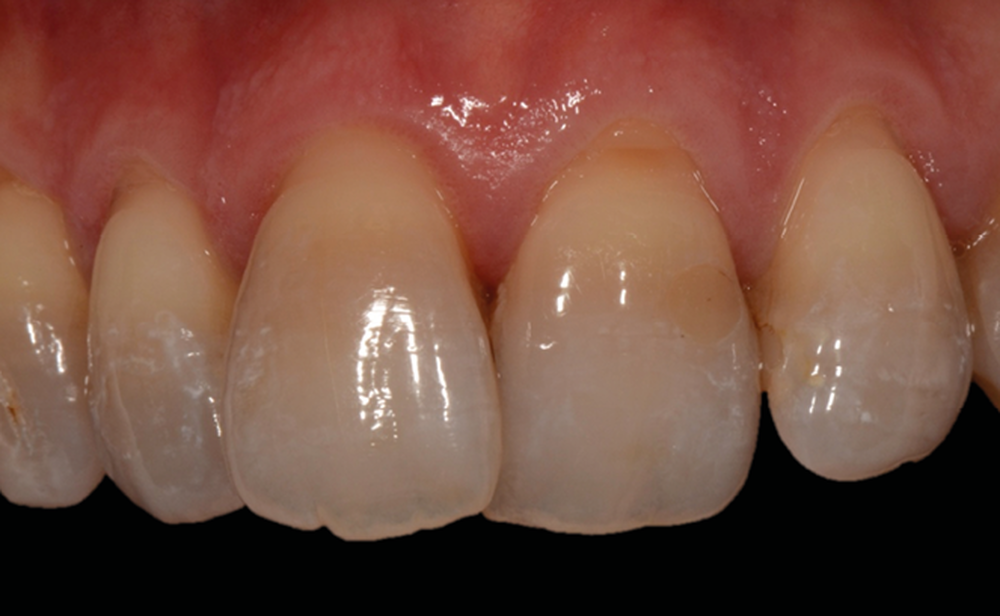

Professeur et chef de service du département de parodontologie et actuellement directeur opérationnel de l’école de médecine dentaire de l’université de Berne, en Suisse, le Pr Sculean est actuellement répertorié comme l’expert le mieux coté en parodontologie dans le monde1. Il est l’auteur du livre Periodontal regenerative therapy consacré aux techniques régénératives contemporaines dans le traitement des défauts osseux et des tissus. Par sa compréhension de l’anatomie du parodonte et des phénomènes de cicatrisation biologique des plaies, sa maîtrise des matériaux régénératifs et des techniques chirurgicales, il nous propose des paradigmes de traitement efficaces et prédictibles. L’objectif est de donner un aperçu des possibilités et des limites de la couverture des récessions en prévention avant ou après un traitement orthodontique. L’utilisation de techniques de greffes tunnelisées permet une couverture prévisible et une augmentation de l’épaisseur des tissus pour les récessions gingivales simples et multiples, tout en assurant une stabilité à long terme. Anton Sculean nous propose une approche clinique rigoureuse et efficace, richement illustrée, qui renouvelle notre collaboration interdisciplinaire avec la parodontologie. Un rendez-vous à ne pas manquer !

C’est à ces questions que nous permettront de répondre les deux premiers conférenciers, parodontologistes : le Dr Béatrice Straub nous présentera le renfort parodontal minéralisé, technique qu’elle a développée et pratique depuis de nombreuses années, pour éviter les préjudices des mouvements orthodontiques à risque, notamment lors des décompensations préchirurgicales (fig. 1a-d) ; le Pr Anton Sculean abordera le thème des greffes, avec leurs indications, les différentes techniques à privilégier et illustrera ses propos par de nombreux cas cliniques aux résultats esthétiques impressionnants.